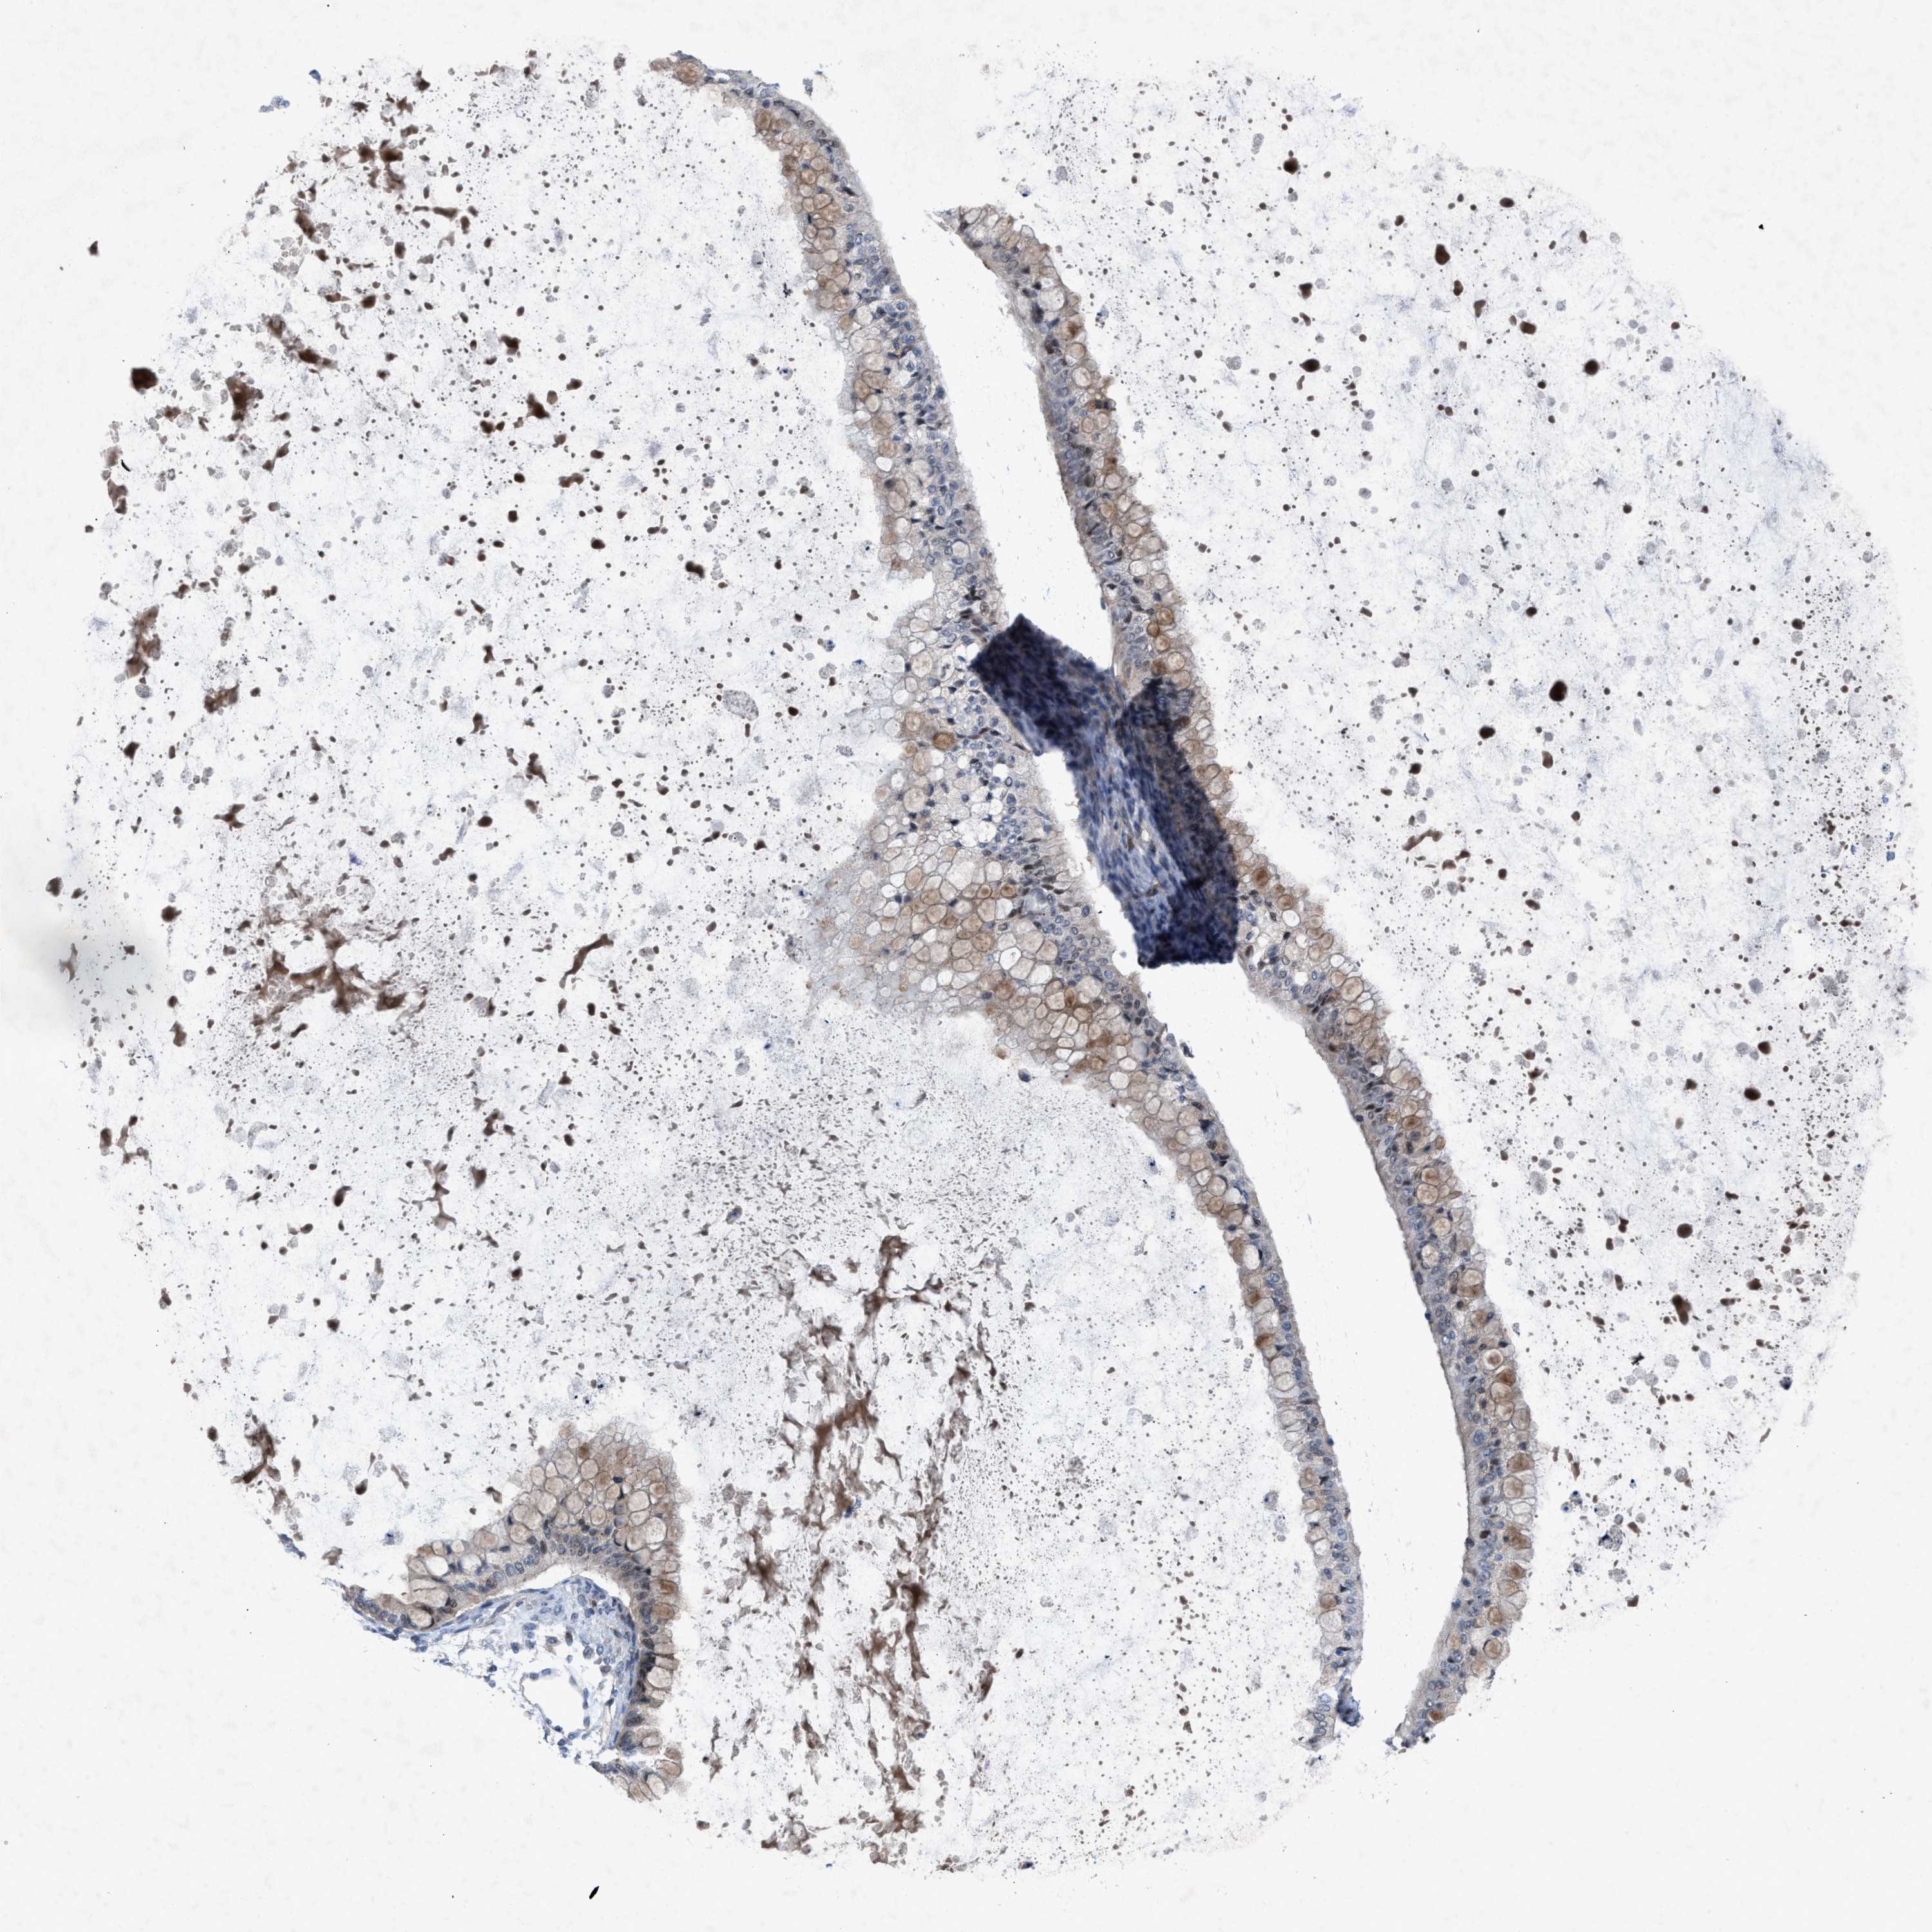

OVARIAN CANCER - Protein expressioni

A mouse-over function shows sample information and annotation data. Click on an image to view it in a full screen mode. Samples can be filtered based on level of antibody staining by selecting one or several of the following categories: high, medium, low and not detected. The assay and annotation is described here.

Note that samples used for immunohistochemistry by the Human Protein Atlas do not correspond to samples in the TCGA dataset.

Antibody stainingi

Antibody staining in the annotated cell types in the current human tissue is reported as not detected, low, medium, or high, based on conventional immunohistochemistry profiling in selected tissues. This score is based on the combination of the staining intensity and fraction of stained cells.

Each image is clickable and will lead to virtual microscopy that enables deeper exploration of all samples and also displays staining intensity scores, fraction scores and subcellular localization as well as patient and tissue information for each sample.

Antibody HPA019011

Staining

High

Medium

Low

Not detected

Intensity

Strong

Moderate

Weak

Negative

Quantity

>75%

75%-25%

<25%

None

Location

Nuclear

Cytoplasmic/membranous

Cytoplasmic/membranous,nuclear

Cystadenocarcinoma, serous, NOS

Carcinoma, endometroid

Cystadenocarcinoma, mucinous, NOS

Carcinoma, NOS